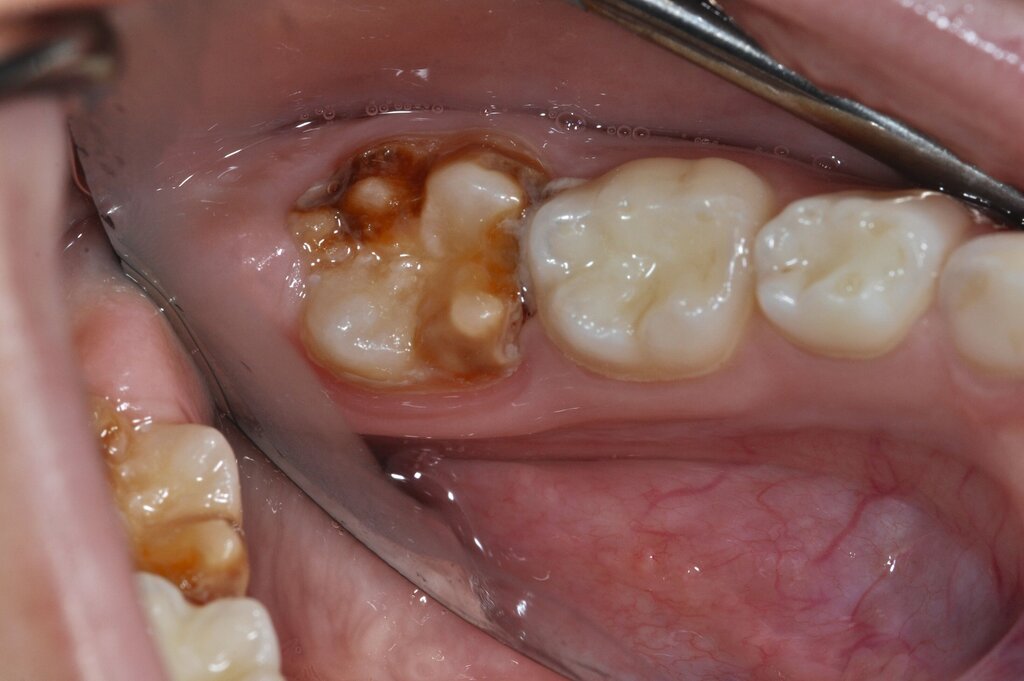

Der Vorteil der Methode ist, dass die betroffenen Zähne auch ohne Lokalanästhesie und Präparation versorgt werden können. Die temporäre Versorgung ermöglicht es, die Patienten an die zahnärztliche Behandlung zu gewöhnen. Häufig führt diese temporäre Versorgung auch zu einer Reduktion der Hypersensitivität der MIH-Zähne. Nachteil der GIZ-Versorgung ist das Risiko einer Füllungsfraktur oder eines vollständigen Verlusts der Füllung (Abbildung 4). Aktuelle Erhebungen bestätigen eine Erfolgsrate von über 80 Prozent nach einem bis zwei Jahren [Durmus et al., 2021; Mahfouz et al., 2025].

Der Behandlungsfall (Abbildung 4d) veranschaulicht die Schwächen des Verfahrens. Wird das Angebot der regelmäßigen Kontrollen nicht wahrgenommen, so droht bei Verlust der Füllung die Kariesprogression. In dem vorliegenden Fall konnte jedoch eine endodontische Maßnahme vermieden und durch die selektive Kariesentfernung die Zahnhartsubstanz weitestgehend erhalten werden.